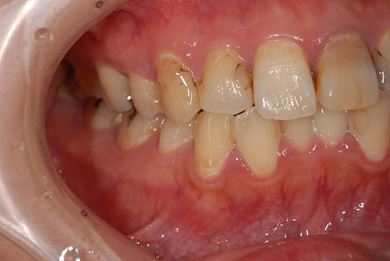

性別/年齢 女性 / 26歳

主訴 虫歯や汚れの治療を希望。

治療方針 セラミック治療にて、審美的回復を行う。

治療前

• 治療前